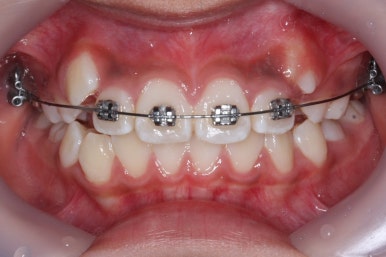

장치를 부착한 후에 순차적으로 변화가 나타나는 모습입니다.

총 4장의 사진 동안 경과한 시간은 불과 6개월 입니다. 헤드기어를 통해 사전에 작업을 해뒀기 때문에 이후 연산동덧니교정 과정은 편해진 것이죠.

윗니만 6개월이 지난 모습입니다.

치열이 매우 가지런해졌죠. 이 후에는 특이사항 없이 종료가 되었습니다.